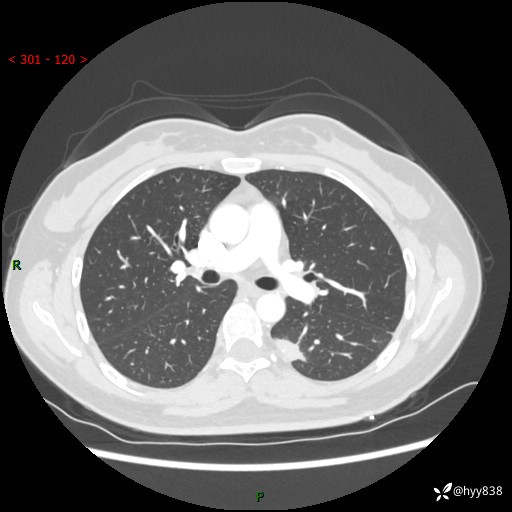

【患者信息】:36岁/女

【主诉】:左侧下胸部阵发性疼痛2周,乏力1周

【现病史及既往史】:患者自诉2周前饮酒后出现左侧下胸部阵发性疼痛,不随呼吸改变,无咳嗽咳痰、头晕头痛、咳血、呼吸困难等不适,于当地第一人民医院查胸部CT提示肺部感染,随后前往我院门诊给予抗感染(左氧氟沙星)治疗1周,自诉胸痛较前好转,感乏力、头晕,偶尔干咳,无咳痰,无发热、畏寒、胸闷、咯血、四肢酸痛、腹泻、腹痛等不适,门诊复查胸部CT提示:左肺下叶感染,病灶较前增加增大,遂以“肺部感染”收入我科。 起病以来,患者精神、饮食、睡眠可,大小便正常,体力体重无明显变化。

【检查】:胸部CT增强(外院平扫)